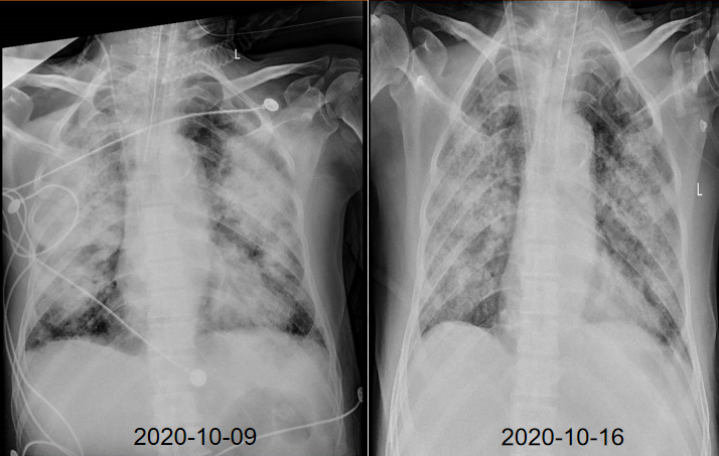

影像改变

患者胸部X线片可见渗出较前有所吸收(图3)

图片

图3  患者影像学改善情况